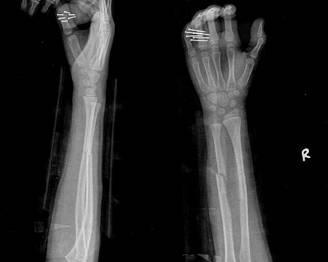

經(jīng)過醫(yī)生的診斷,小明被確診為尺橈骨融合,這是一種骨骼疾病,會導(dǎo)致尺骨和橈骨無法正常活動,聽到這個消息后,小明和他的朋友們都感到有些緊張和害怕,但他們并沒有放棄,而是選擇相互鼓勵,共同面對這個挑戰(zhàn)。

在醫(yī)生的介紹下,他們了解到了一種最新的尺橈骨融合治療方法——通過微創(chuàng)手術(shù)進行骨骼融合的新技術(shù),這種方法不僅減少了手術(shù)風(fēng)險,還能更快地恢復(fù)活動能力,雖然小明感到害怕,但他的朋友們一直陪伴在他身邊,給予他勇氣和力量。